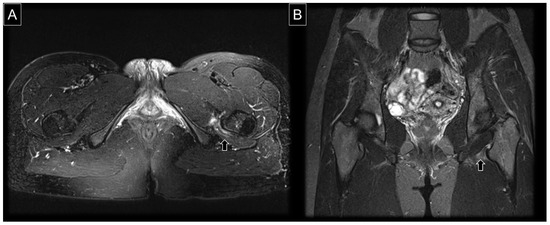

7. MRI Assessment